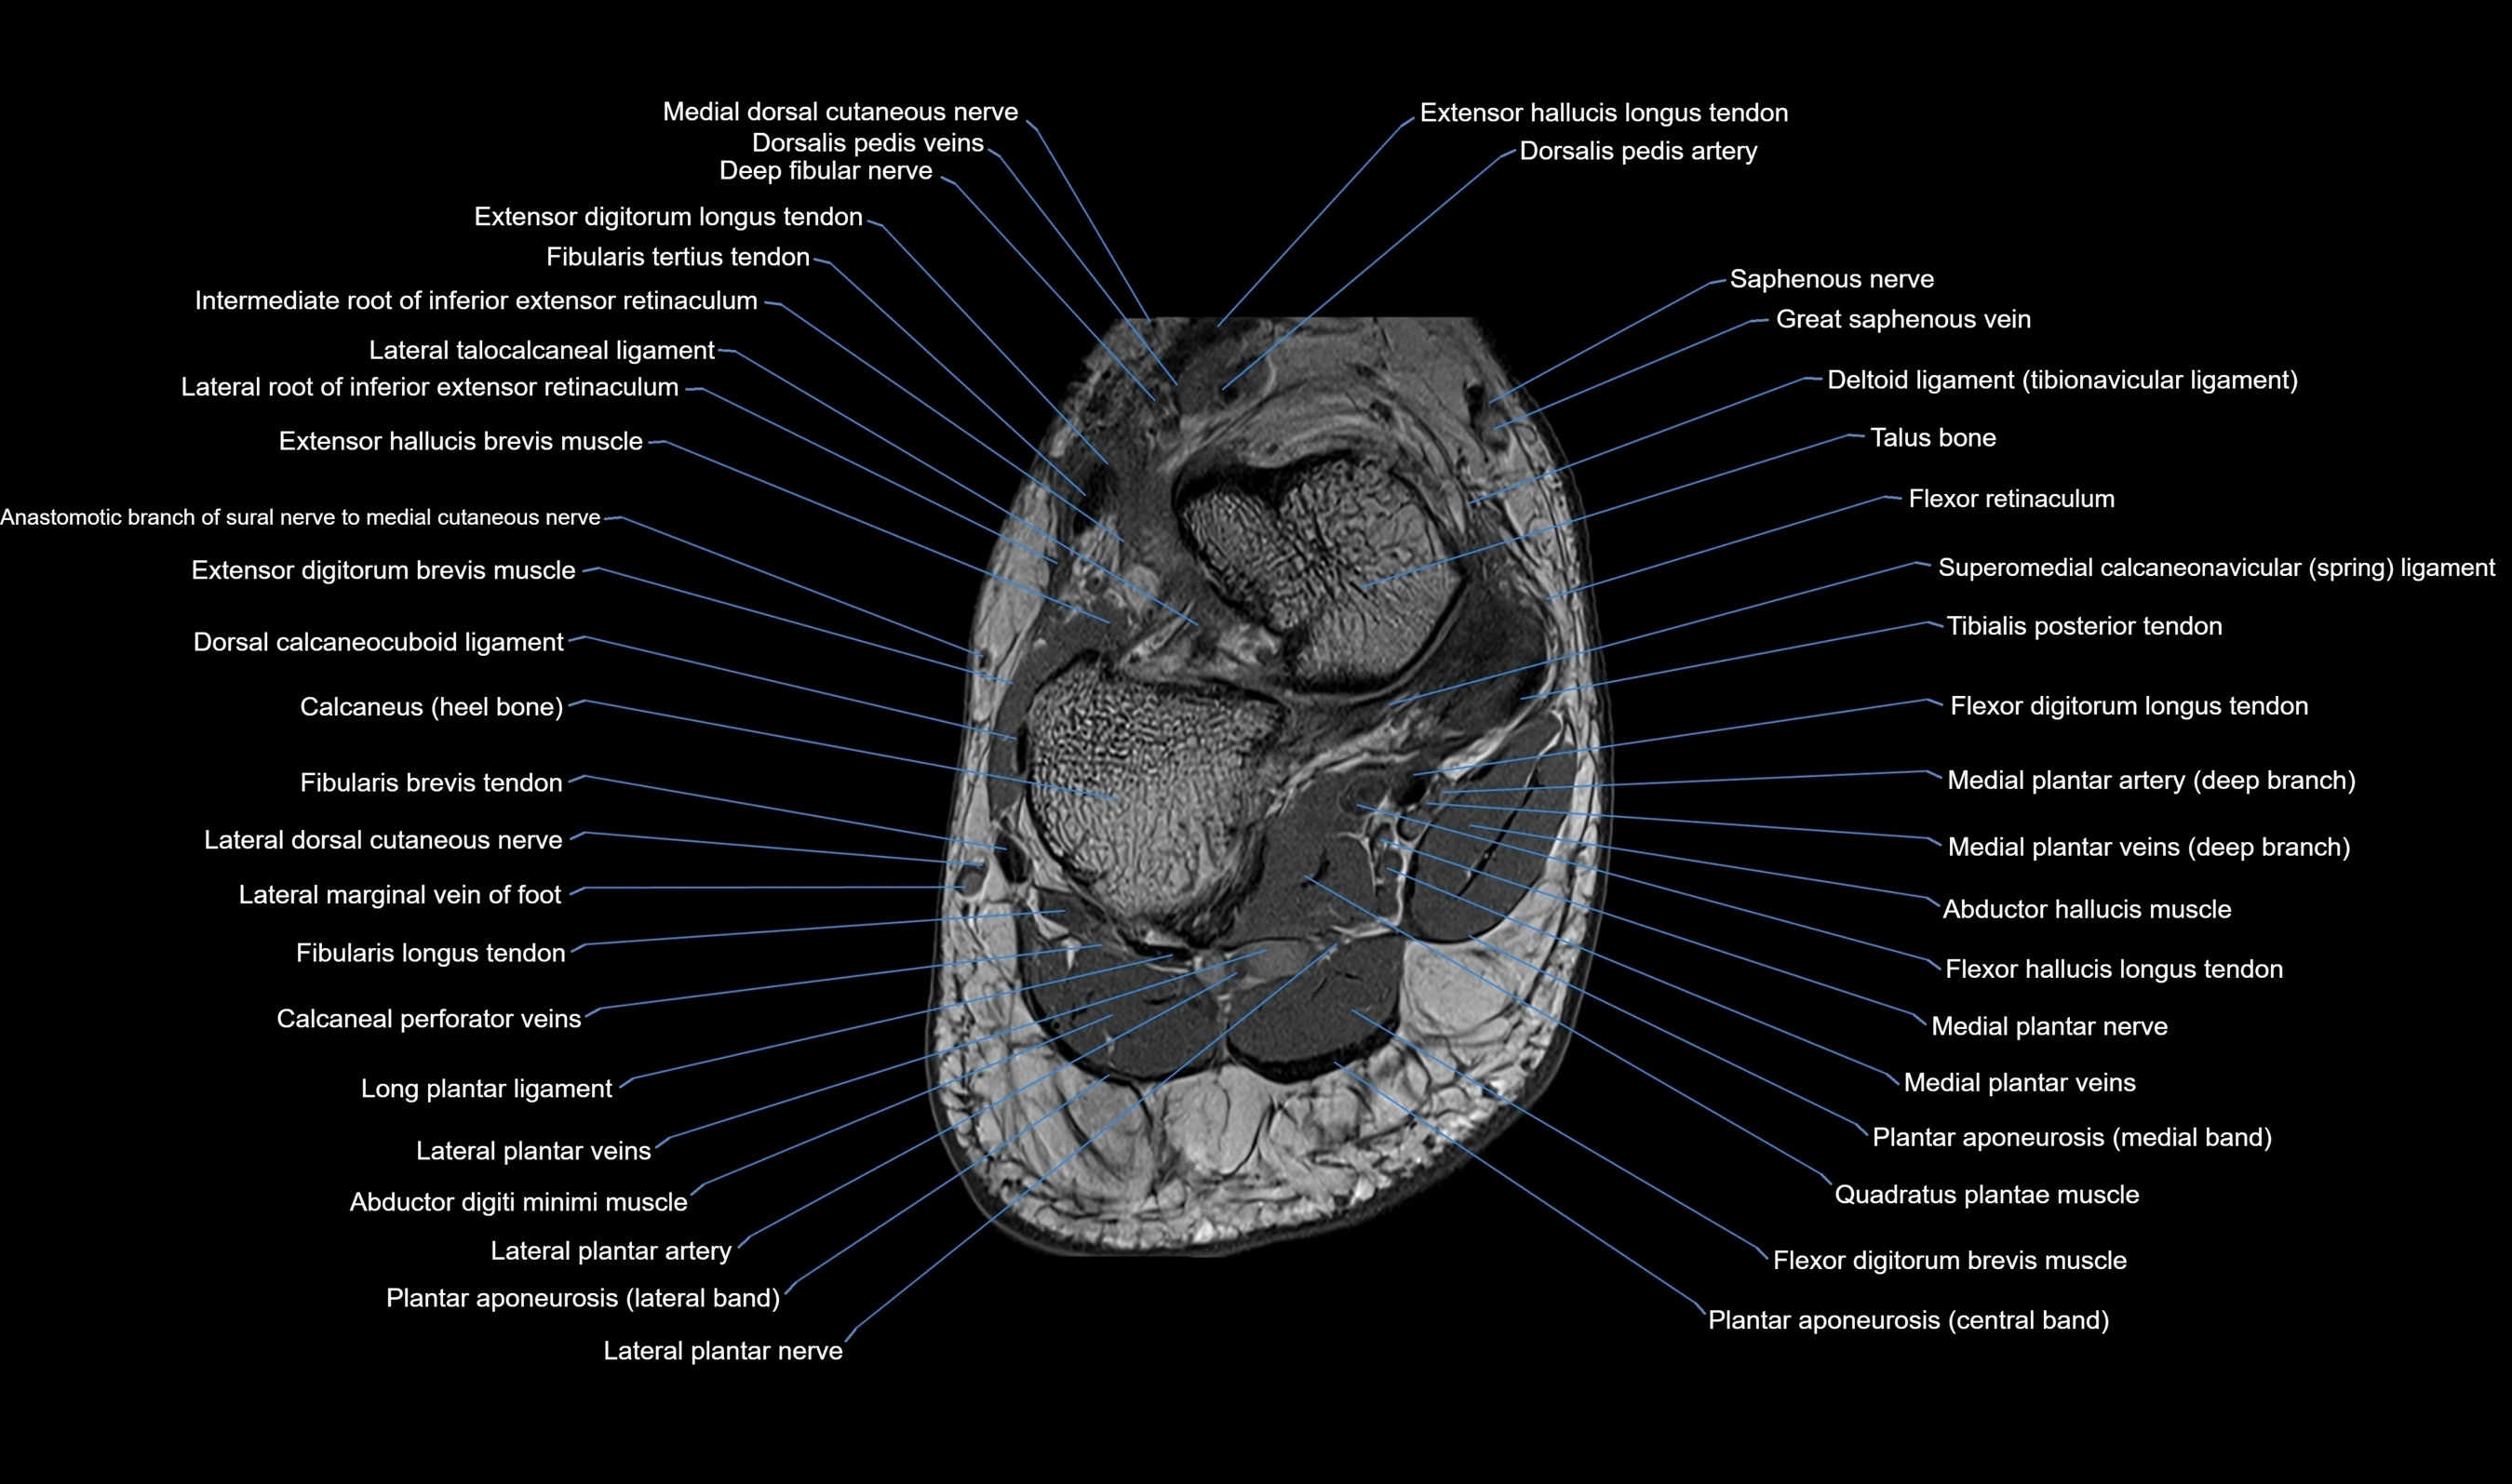

MRI image